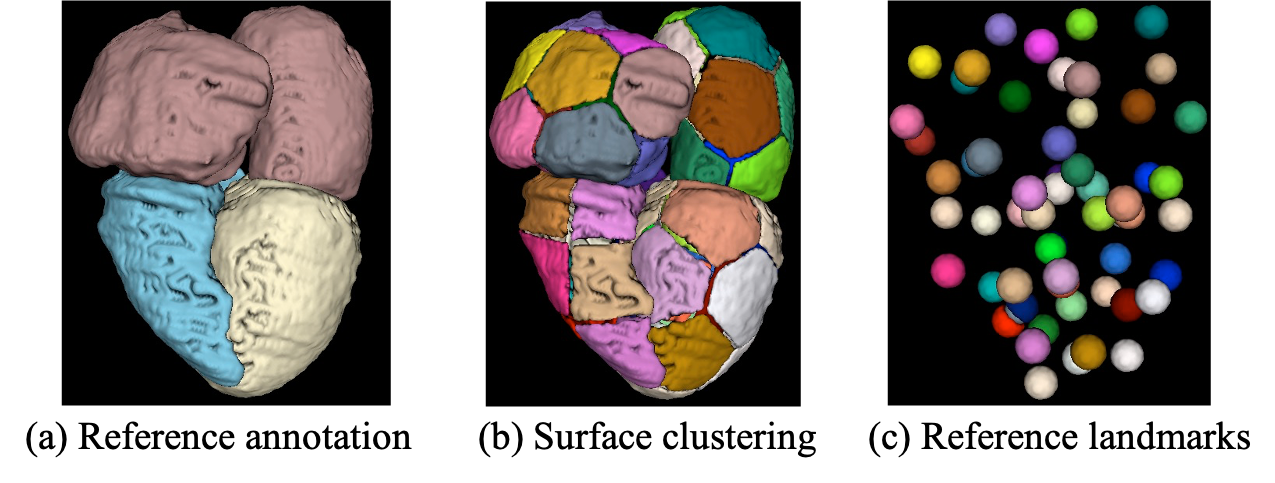

Refer to caption

Figure 5: Reference point distribution: (a) surface visualization of the reference annotations (from an atlas); (b) subgroup annotations with different colors after k-means clustering; (c) Reference points are derived as the center points of the clusters.

Fig. 5 depicts the process to extract the reference landmarks. We first choose an atlas downloaded from the public cardiac segmentation dataset 222https://zmiclab.github.io/projects/mmwhs. It is worthy to note that we only utilize a single atlas and the annotation, which can sufficiently establish reference point distribution in our work. Then, we extract the surface from the annotated segmentation as shown in Fig. 5(a). The extracted surface represents the structural topology of the target organ. Next, we use k-means [56] to cluster the points on the surfaces based on their 3D coordinates, which produces several subgroups as shown in Fig. 5(b). Finally, the center of each subgroup is used as the reference point distribution to represents the anatomical topology of the target organ as a whole (see Fig. 5(c)).